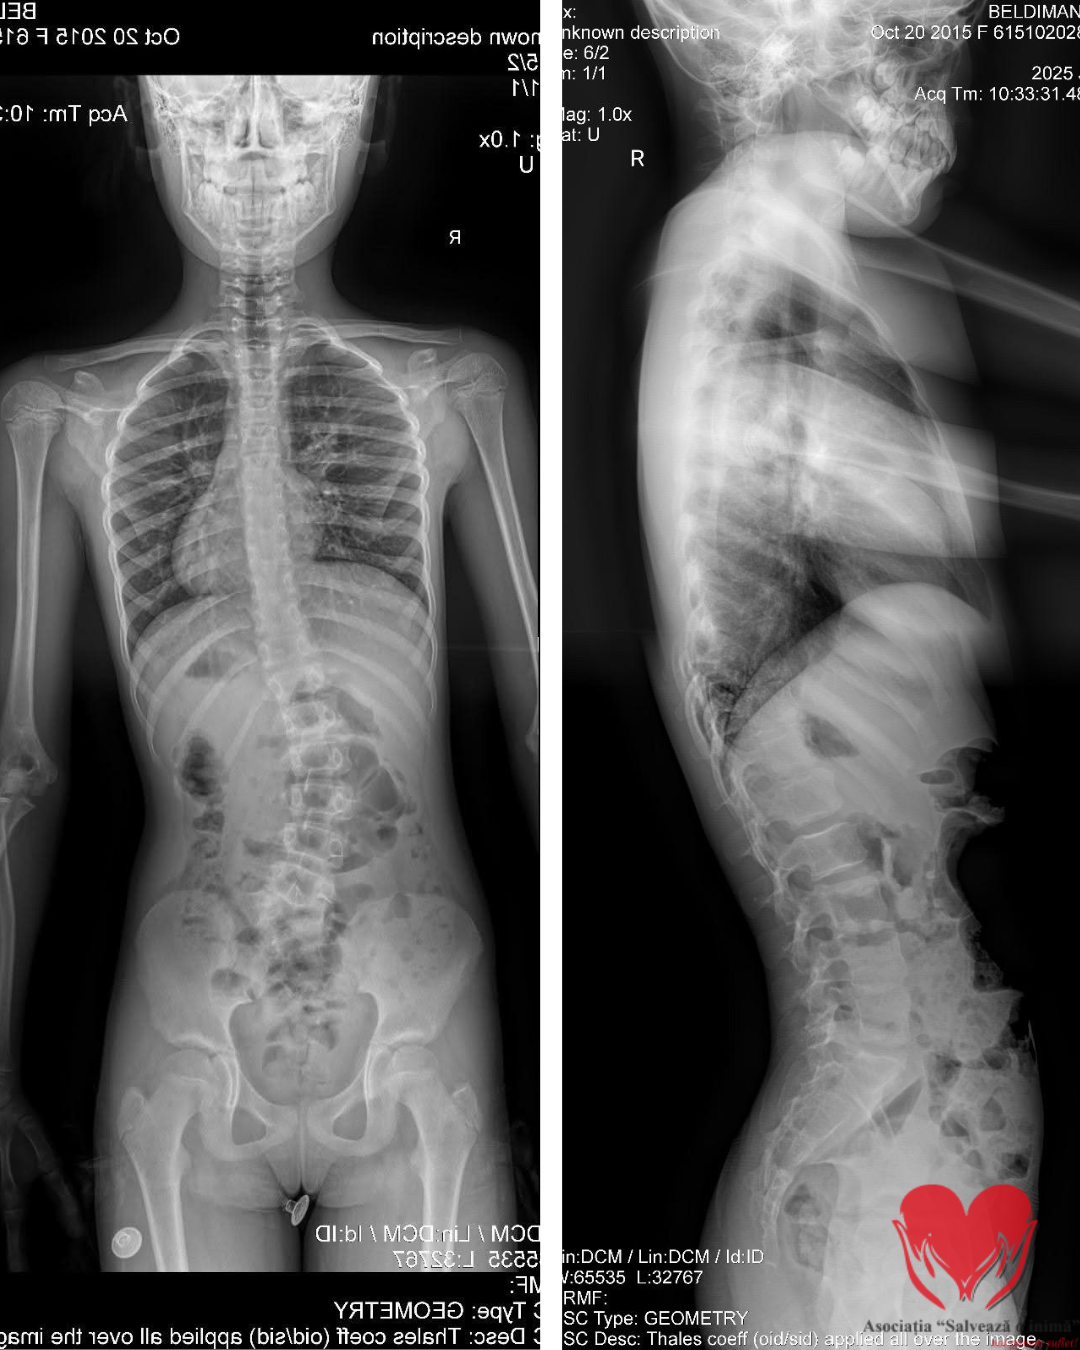

Eva Maria Raluca Beldiman are 10 ani. În scrisoarea medicală scrie simplu vârsta și diagnosticul: hemivertebră lombo-sacrată L5 stânga complet segmentată. În realitate, povestea ei înseamnă mult mai mult decât un cod medical.

Totul a fost descoperit întâmplător, la 5 ani, în urma unei radiografii. Medicii căutau un bănuț înghițit accidental. Au găsit însă altceva: o coloană care nu creștea drept. În timp, investigațiile au confirmat scolioza toraco-lombară, iar cauza a devenit clară – o vertebră formată incomplet, care împinge coloana să se deformeze progresiv.

În interior, însă, fiecare lună înseamnă o curbură care poate avansa. Fără intervenție chirurgicală – hemivertebrectomie prin tehnica Ruf-Harms – deformarea va continua. Cu intervenția, există șansa unei dezvoltări normale.